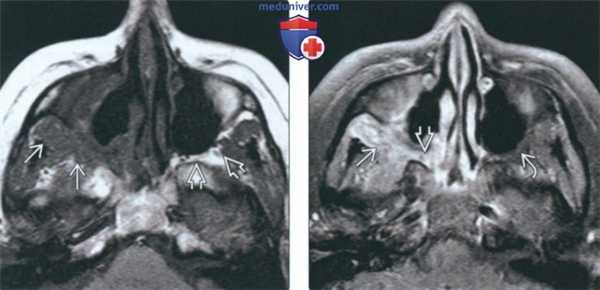

Гранулематоз Вегенера (МРТ) после хирургического вмешательства на придаточных пазухах. При контрастировании мягких тканей выявляется внутриглазничное и внутричерепное распространение гранулематозного процесса.

• Т1 ВИ С+:

о Равномерное контрастирование

о Утолщение и контрастное усиление оболочек мозга

о Если на КТ или клинически заподозрено поражение глазницы, глубоких тканей лица, основания черепа или оболочек мозга:

- МРТ с контрастным усилением и жироподавлением